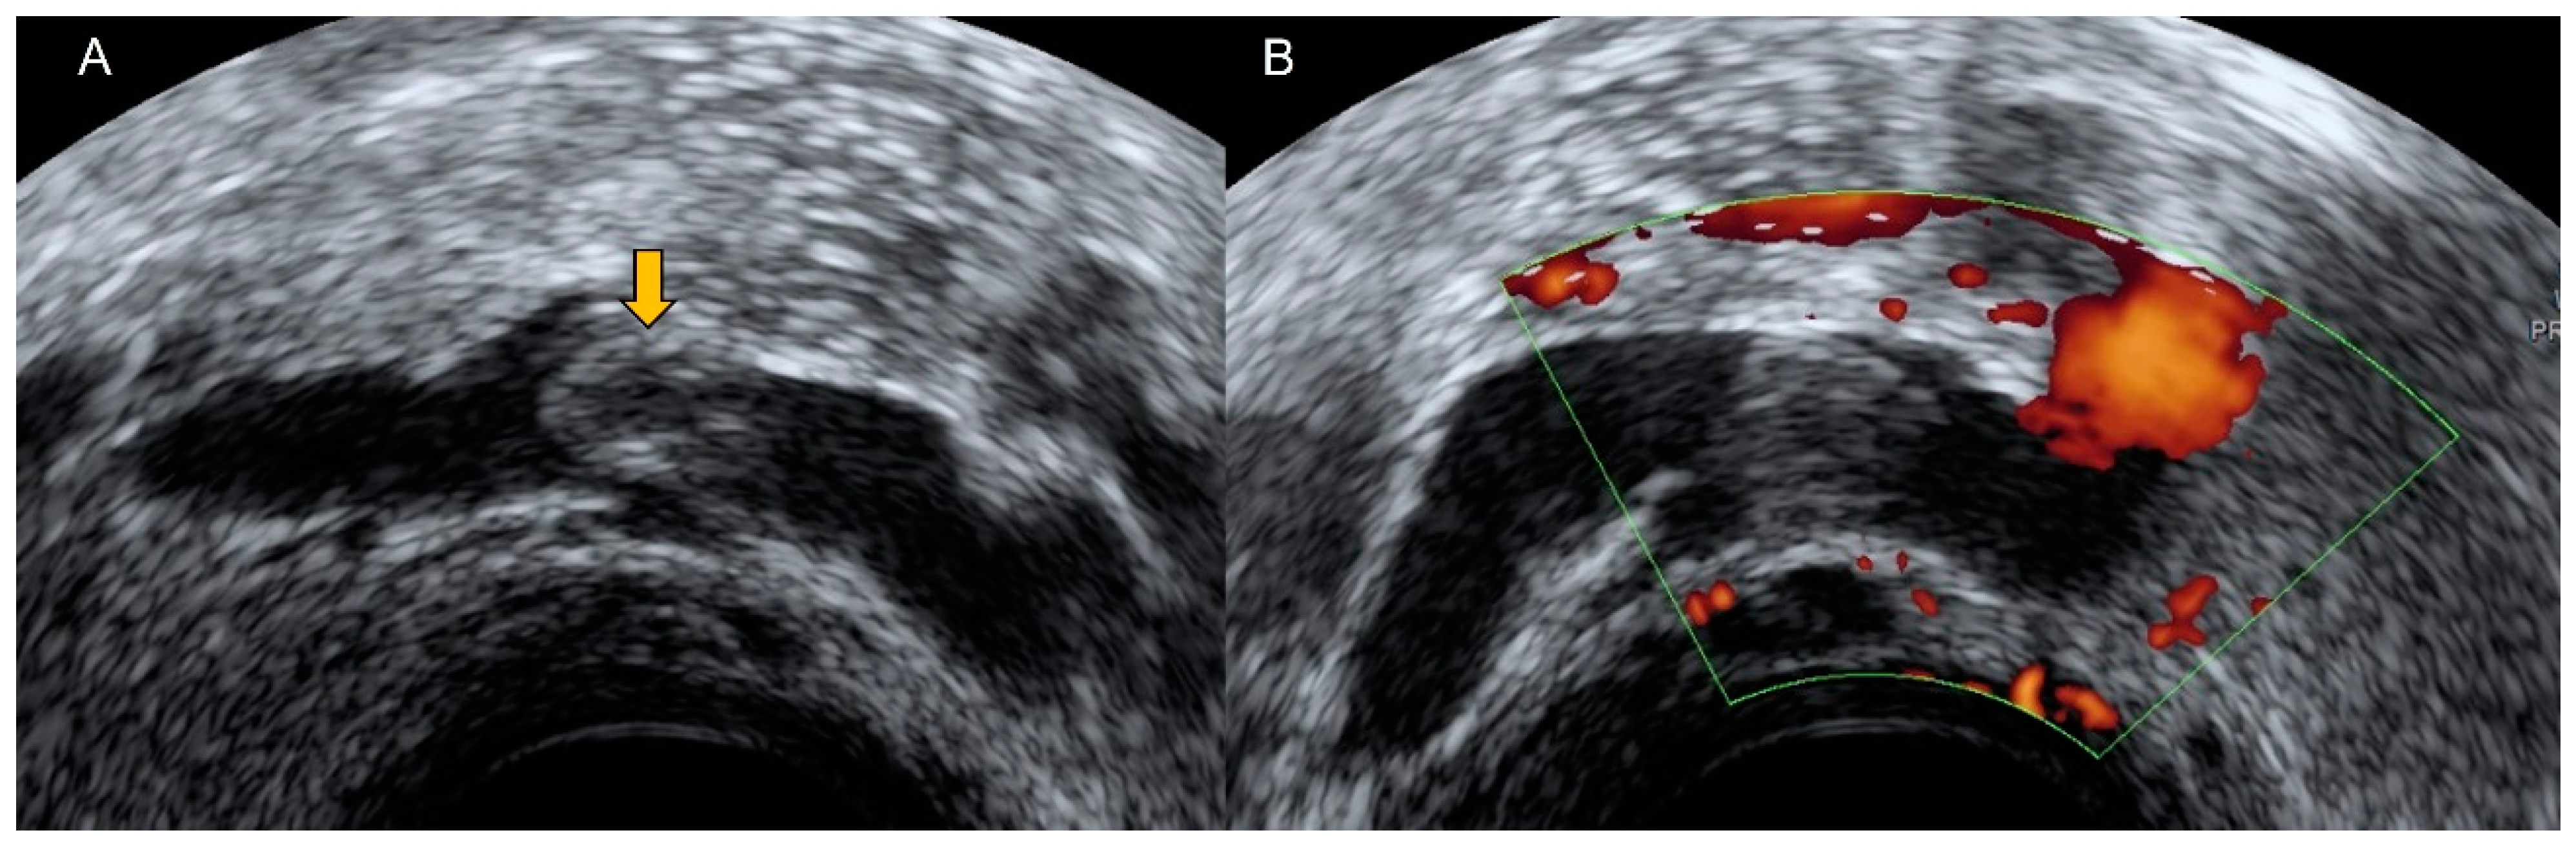

4.3. Aneurysm

- Parry, D.J.; Kessel, D.; Scott, D.J.A. Simplifying the internal iliac artery aneurysm. Ann. R. Coll. Surg. Engl. 2001, 83, 302–308. [Google Scholar]